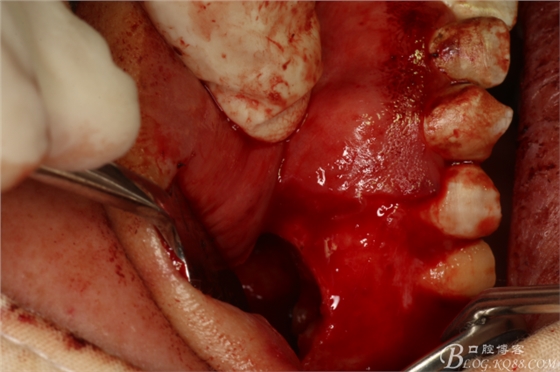

圖9.暴露出16根尖上方的囊壁